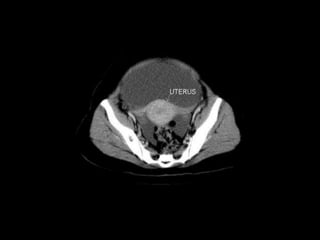

Pelvic peritoneal space Thepelvic peritoneal space is the inferior reflection of the peritoneum over the fundus of the urinary bladder and the front of the rectum at the junction of its middle and lower thirds. In females, the reflection is also over the anterior and posterior surface of the uterus and the upper posterior vagina.In males there is only one potential space for fluid collection posterior to the bladder, the rectovesical pouch. In females there are two potential spaces posterior to the bladder, the uterovesical pouch, and posterior to the uterus the deeper rectouterine pouch (pouch of Douglas). The layers of peritoneum on the anterior and posterior surfaces of the uterus are reflected laterally to the pelvic side walls as the broad ligaments, containing thefallopian tubes.